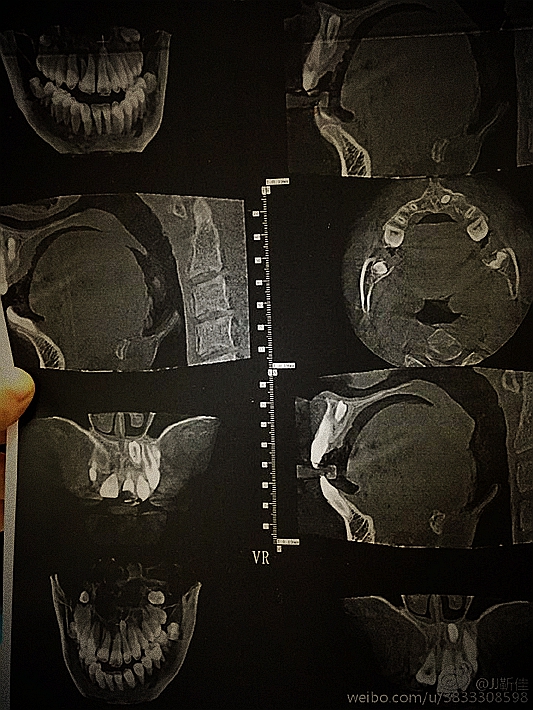

ct定位

額外牙拔除

好大的額外牙

植入骨膏

覆蓋骨膜

縫合

術(shù)后拍片